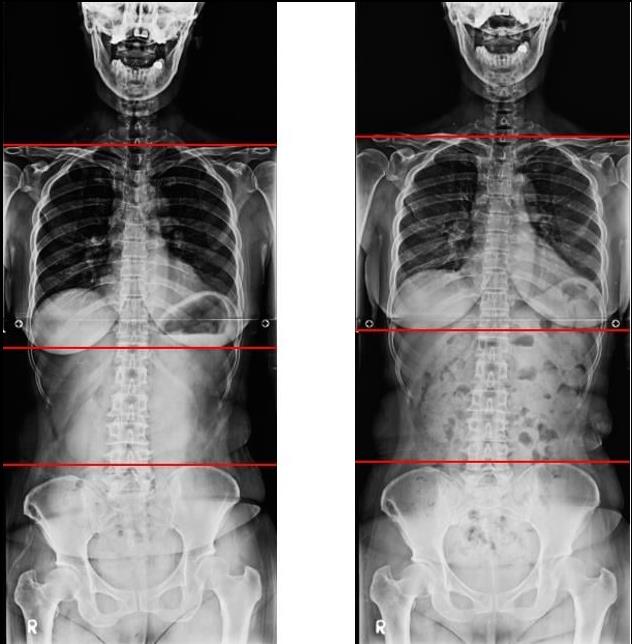

The following x-ray is of a patient who was treated for discomfort in the temporomandibular joint, who underwent short-term mcb splint treatment.

Until now, the deviation of patients who visited the hospital has always been the same pattern.

The right shoulder is rotating backward, and the left pelvis is rotating backwards.

In this movement, when the mcb splint is installed, the shoulder that was narrowed forward is stretched backward, and the right shoulder that moved backward moves forward.

And the left pelvis, which was moving backwards, begins to move forward.

At the same time, the spine moves straight as all the muscles move upwards instead of downwards.

These movements are consistent with the direction of deflection in scoliosis.